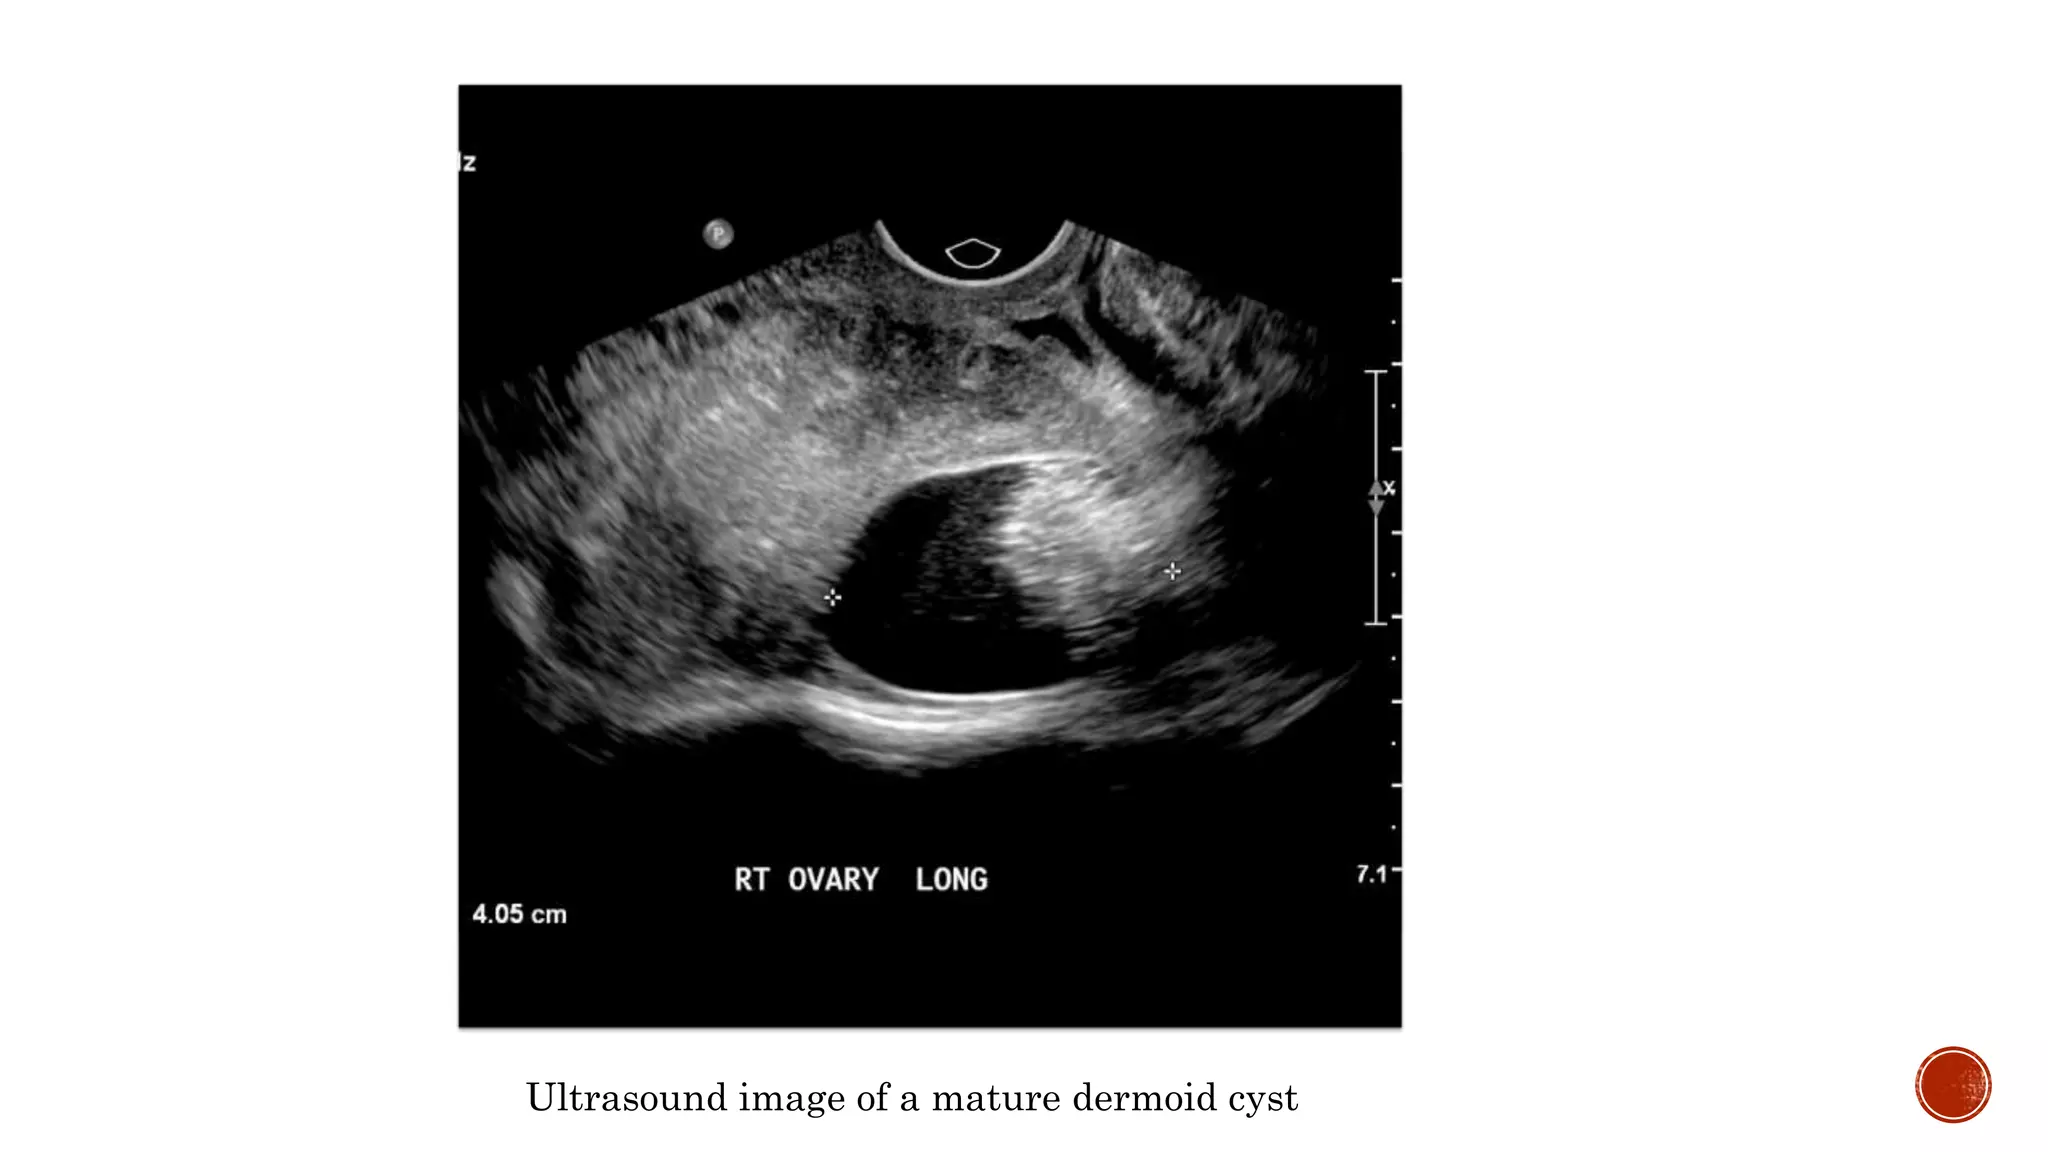

Ultrasound image of a mature dermoid cyst

US Rokitansky nodule Echogenic area CT Fatattenuation, with/without calcification in the wall MRI Sebaceous component has a very high signal for T1 Fat attenuation, T2

Ultrasound image ofa mature dermoid cyst